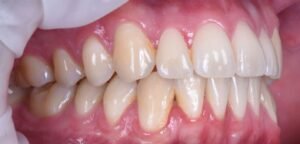

Het resultaat: een herstelde glimlach en meer levenskwaliteit

Na afronding van het traject en het plaatsen van de definitieve kroon kon onze patiënt meteen weer alles doen wat hij gewend was. De nieuwe tand functioneert als een normale tand — de pijn en klachten verdwenen en zijn zelfvertrouwen keerde terug. Een implantaat biedt niet alleen een esthetische verbetering, maar draagt ook merkbaar bij aan uw dagelijkse kwaliteit van leven:

Met een implantaat vervangt u een ontbrekende kies op een duurzame manier, zonder dat andere tanden daarbij beschadigd hoeven te raken.